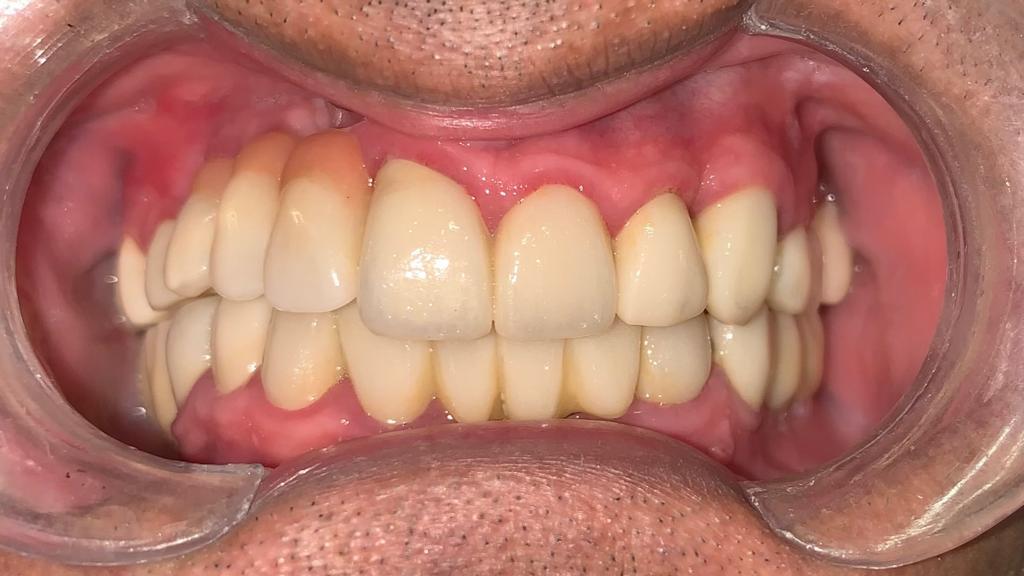

Fase 4: Resultado final de la rehabilitación oral completa

Fase 4

Rehabilitación Completa

Resultado final con prótesis fija e implantes dentales, restaurando función masticatoria, estética y calidad de vida del paciente.